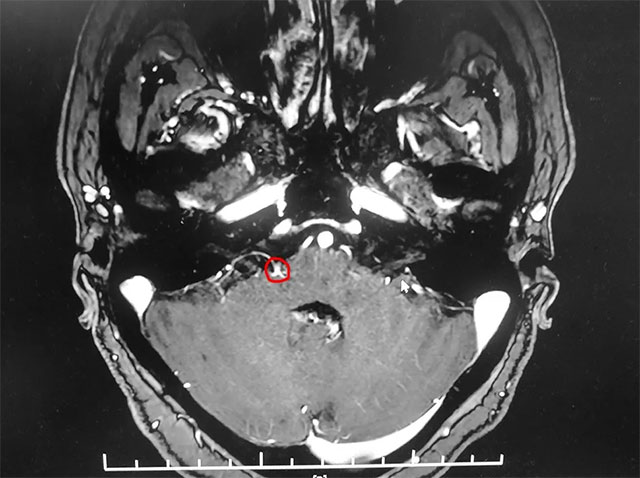

▲ 患者右侧面神经与周围小血管关系密切

入院后,经面神经MRTA平扫+增强检查显示,患者右侧面神经与周围小血管关系密切。在对患者病情及影像学资料进行评估,并告知患者及家属手术风险后,上海蓝十字脑科医院神经外科主任沈建康教授团队为患者实施了面神经微血管减压手术。